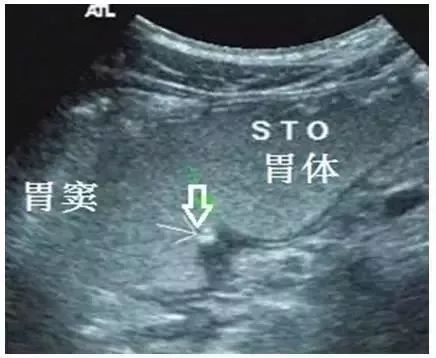

2. 愈合期:溃疡深度<3mm,周缘胃壁厚度<5mm,范围<15mm(图5)。

图5 胃角溃疡(愈合期,箭头所示)